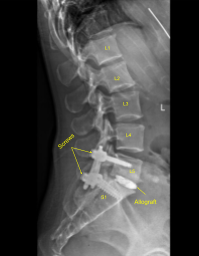

Morselized autograft selected during the decompression as well as morselized allograft was funneled into the interspace with funnel and tamp and then titanium interbody spacer was gently tamped into the interspace under fluoroscopic guidance and expanded into proper position. AP and lateral fluoroscopy showed appropriate positioning.

Next, additional CT scan was obtained showing slightly medial position of the left L5 guidewire. Therefore, Jamshidi navigation was again used to re-cannulate the left L5 pedicle into optimal position. the cannulated navigated pedicle screws were placed over the K wires and K wires were removed with at left L5 and S1 accomplishing a non segmental instrumentation.

These were placed with inserters across the extender tabs and tulips at bilateral L5-S1 pedicle screws under fluoroscopic guidance and secured with locking caps which were finally tightened with torque and anti-torque device after removing the inserters. Extender taps were removed with the breaker device. Hemostasis again confirmed.

The dermal layers were closed with 2-0 Vicryl sutures. The skin incisions were closed with running 4-0 Monocryl subcuticular sutures, cleaned, dried sterilely, and dressed with Dermabond glue. The Dermabond was also applied for the iliac crest array Schanz pin incisions. We did obtain a final CT scan and final x-rays showing correct positioning of all the hardware.